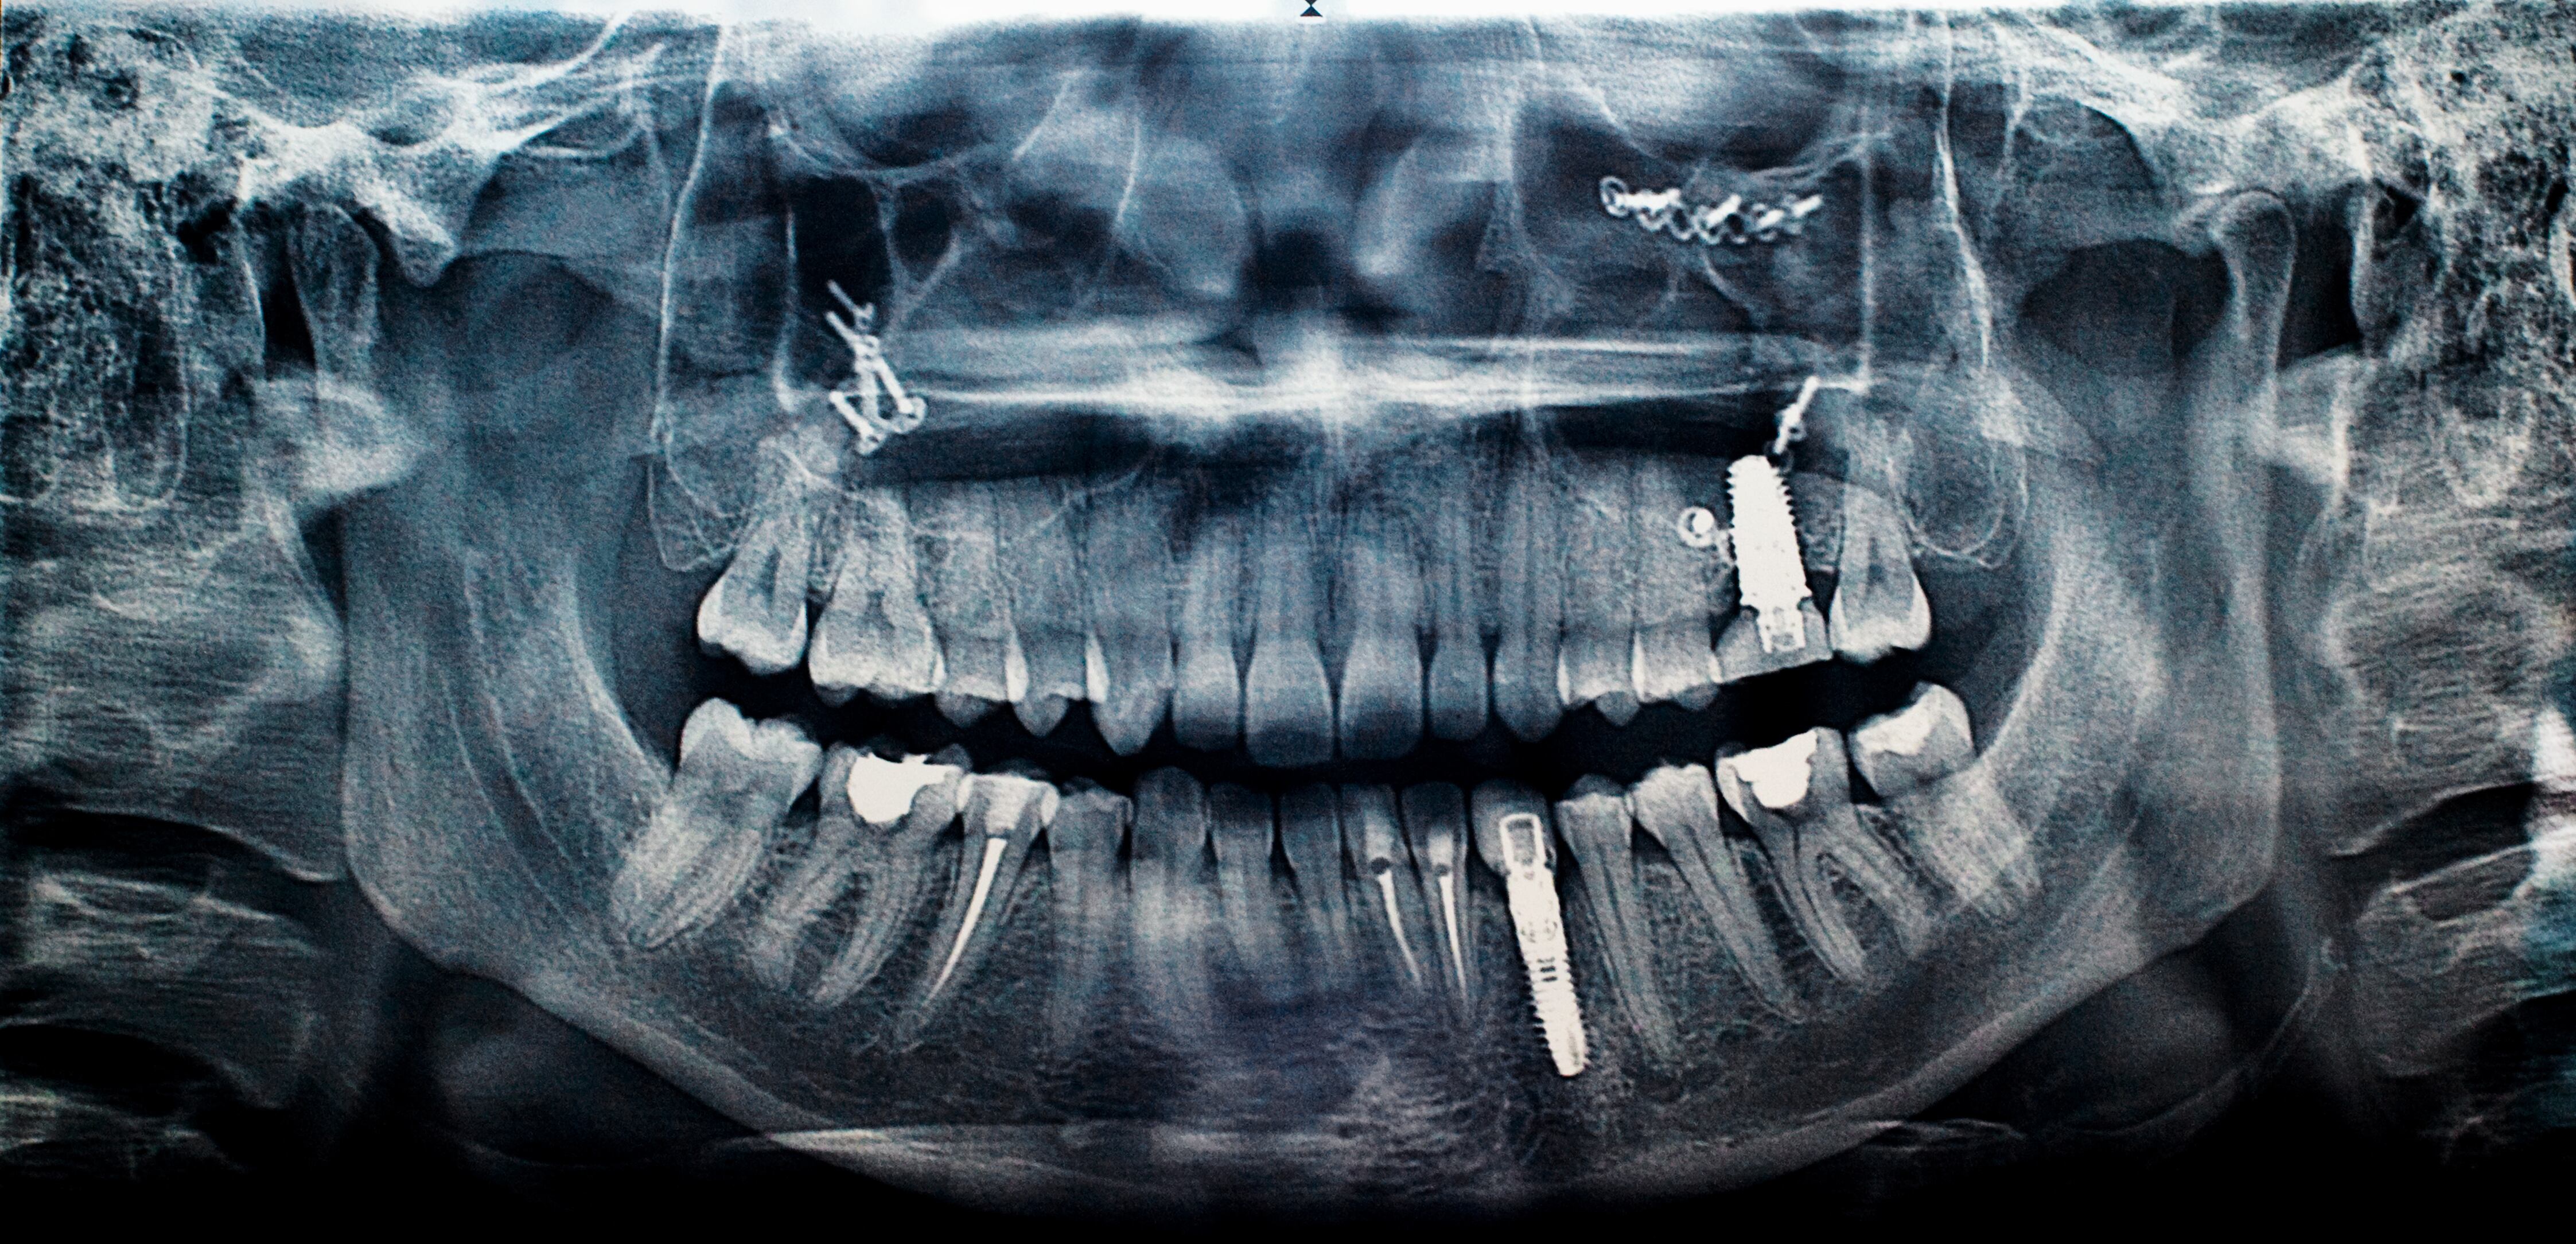

Williams’ dental problems stem from an injury he suffered in 2006 during a roadside bomb attack in Ramadi, Iraq. The blast threw him face-first into his weapon mount, cracking the upper bones in his mouth.

Williams thought the $12,000 fix was a permanent one. But early last summer, he was at a meeting at the Ukrainian embassy in Washington, D.C., when his rebuilt upper teeth fell into his palm mid-sentence.

After hours of calls, Williams managed to locate a dentist who could deal with his immediate health problems and stabilize his mouth. But getting his mouth put back together would require more lengthy surgeries, including drilling new anchors into his skull to permanently hold the teeth in place.